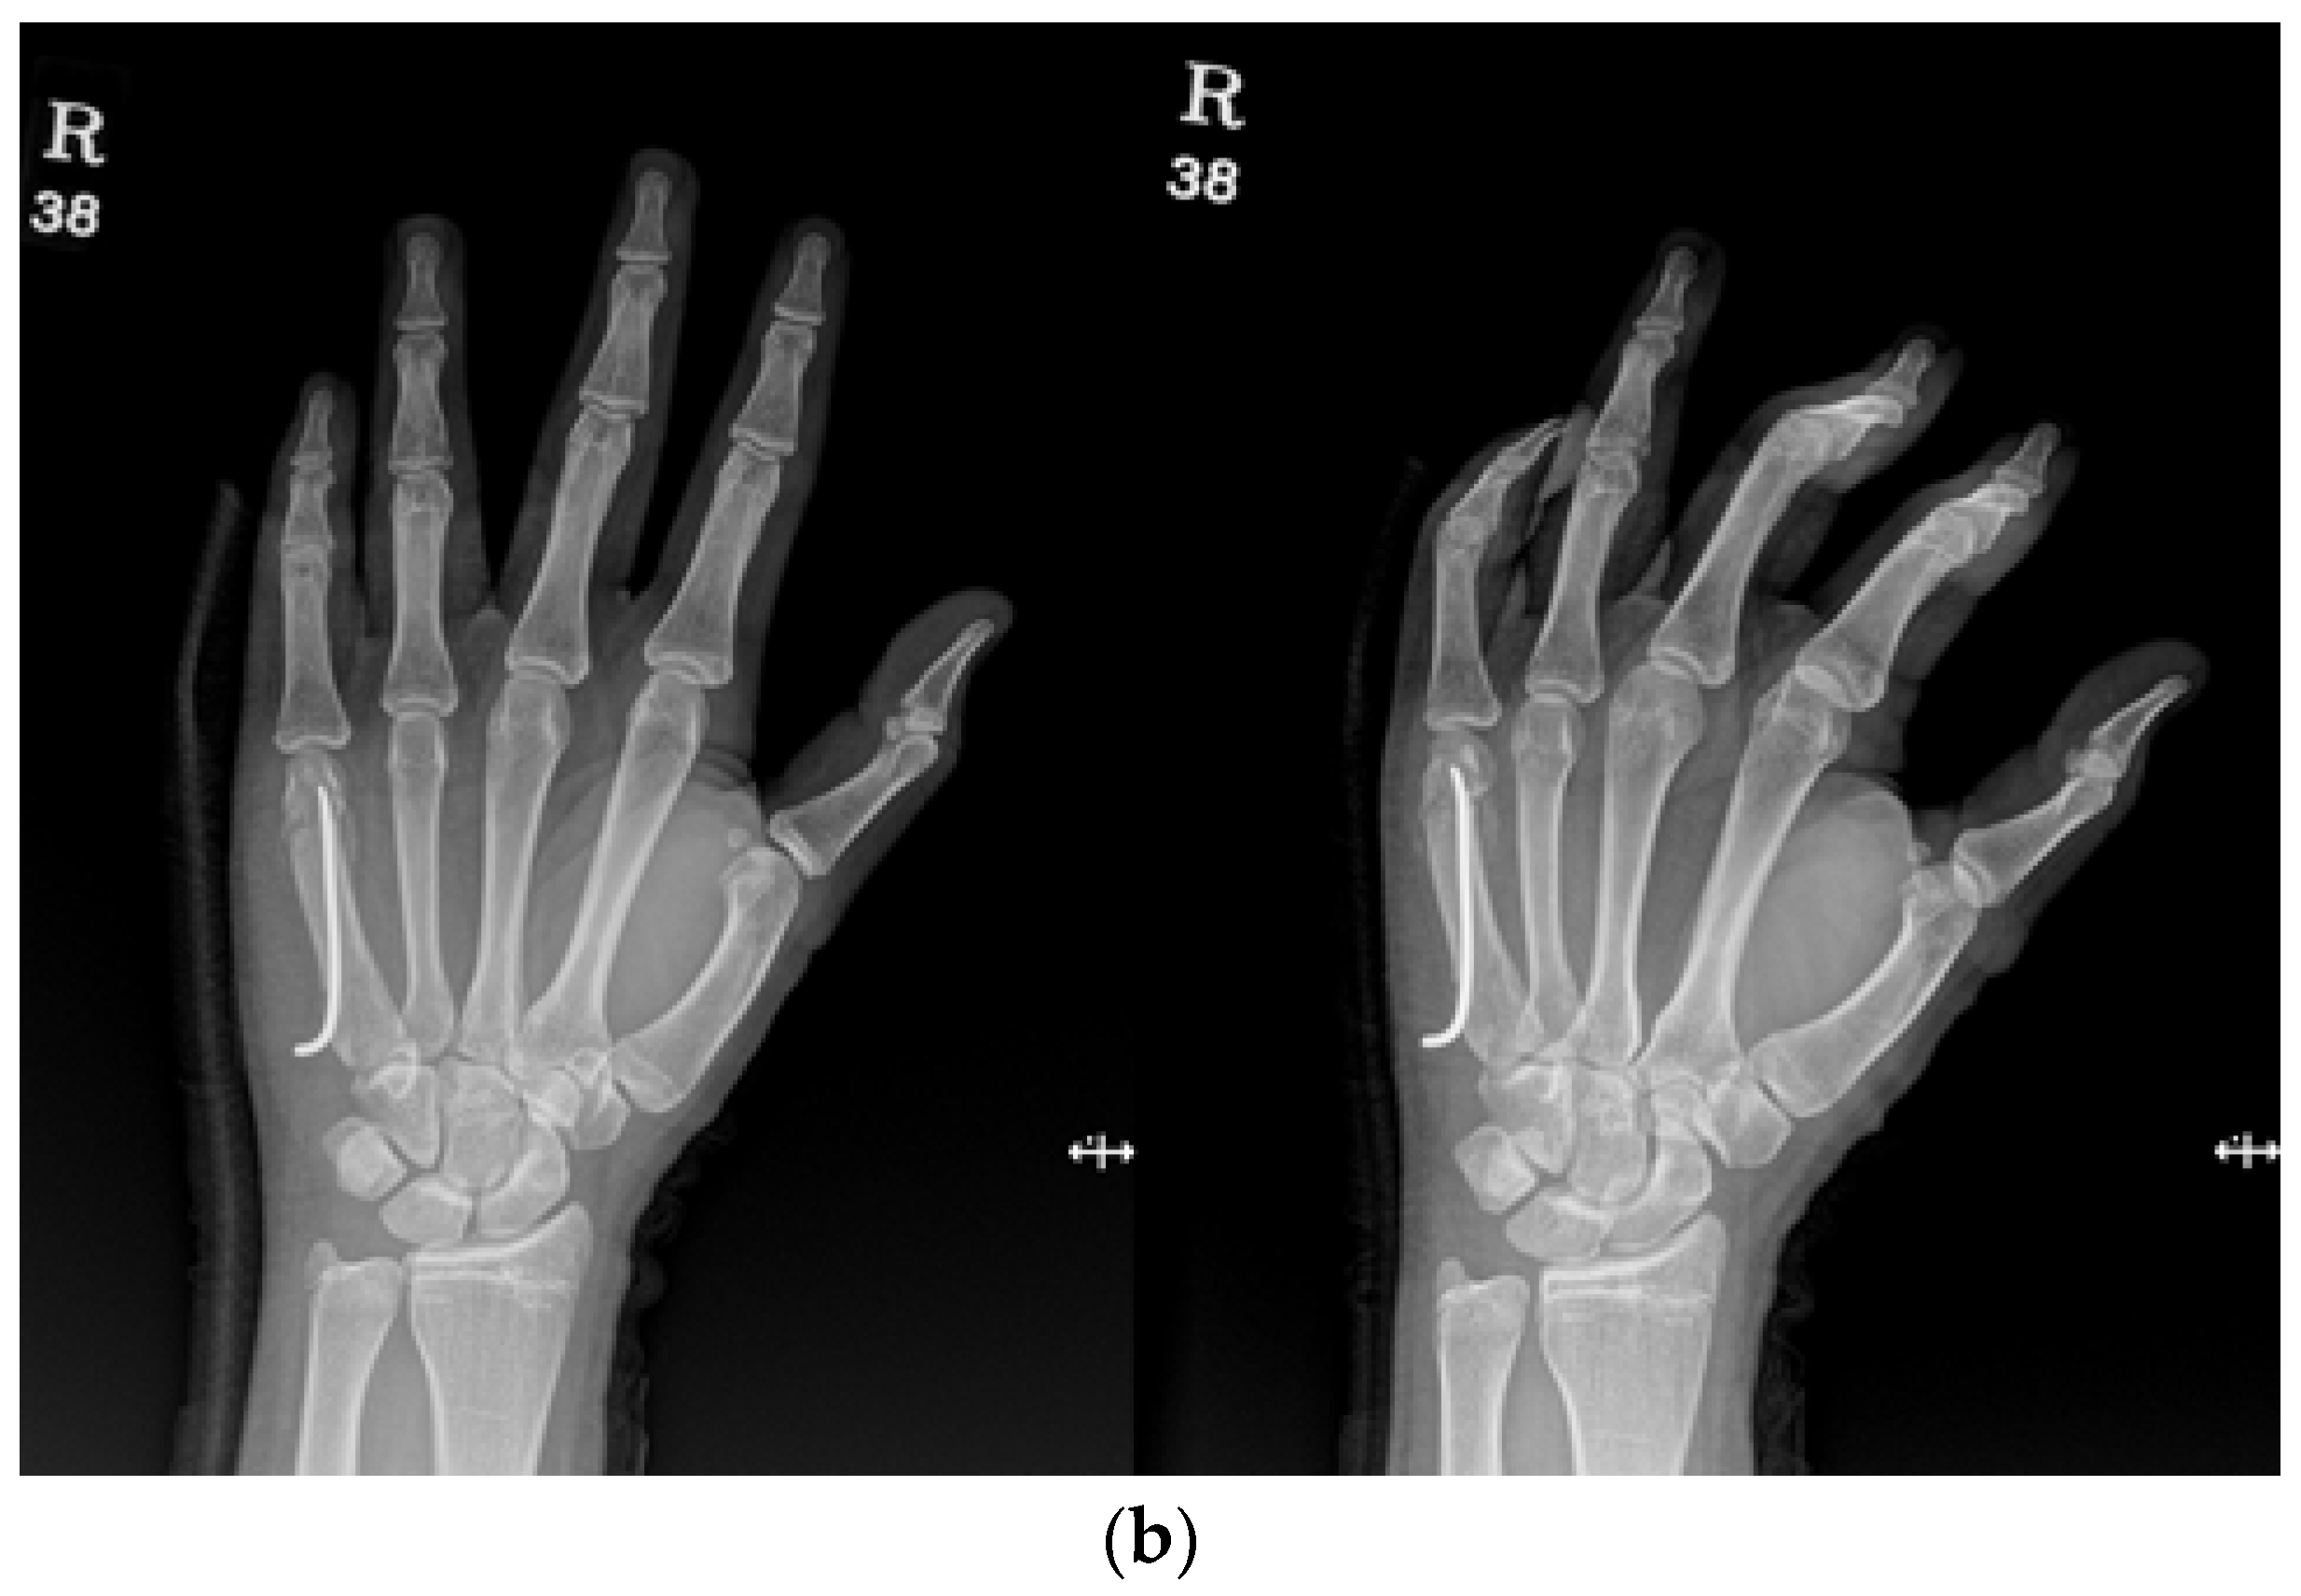

The combined method involved the placement of an intramedullary pin followed by parallel K-wire fixation. Initially, an intramedullary nail was inserted into the metacarpal bone to stabilize the fracture, typically through the base. Following intramedullary pinning, K-wires were placed across the distal part of the intramedullary nail, and the pin was inserted halfway through the dorsal aspect of the nail, touching the nail and making an additional accurate reduction possible. Another pin was inserted on the volar aspect of the nail (Figure 3a,b).

Figure 3.

(a) Radiograph of an 18-year-old male patient with displaced little-finger metacarpal neck fracture. (b) Radiograph of a 16-year-old male patient who underwent the IPKP method using one intramedullary nail and two additional K-wires.